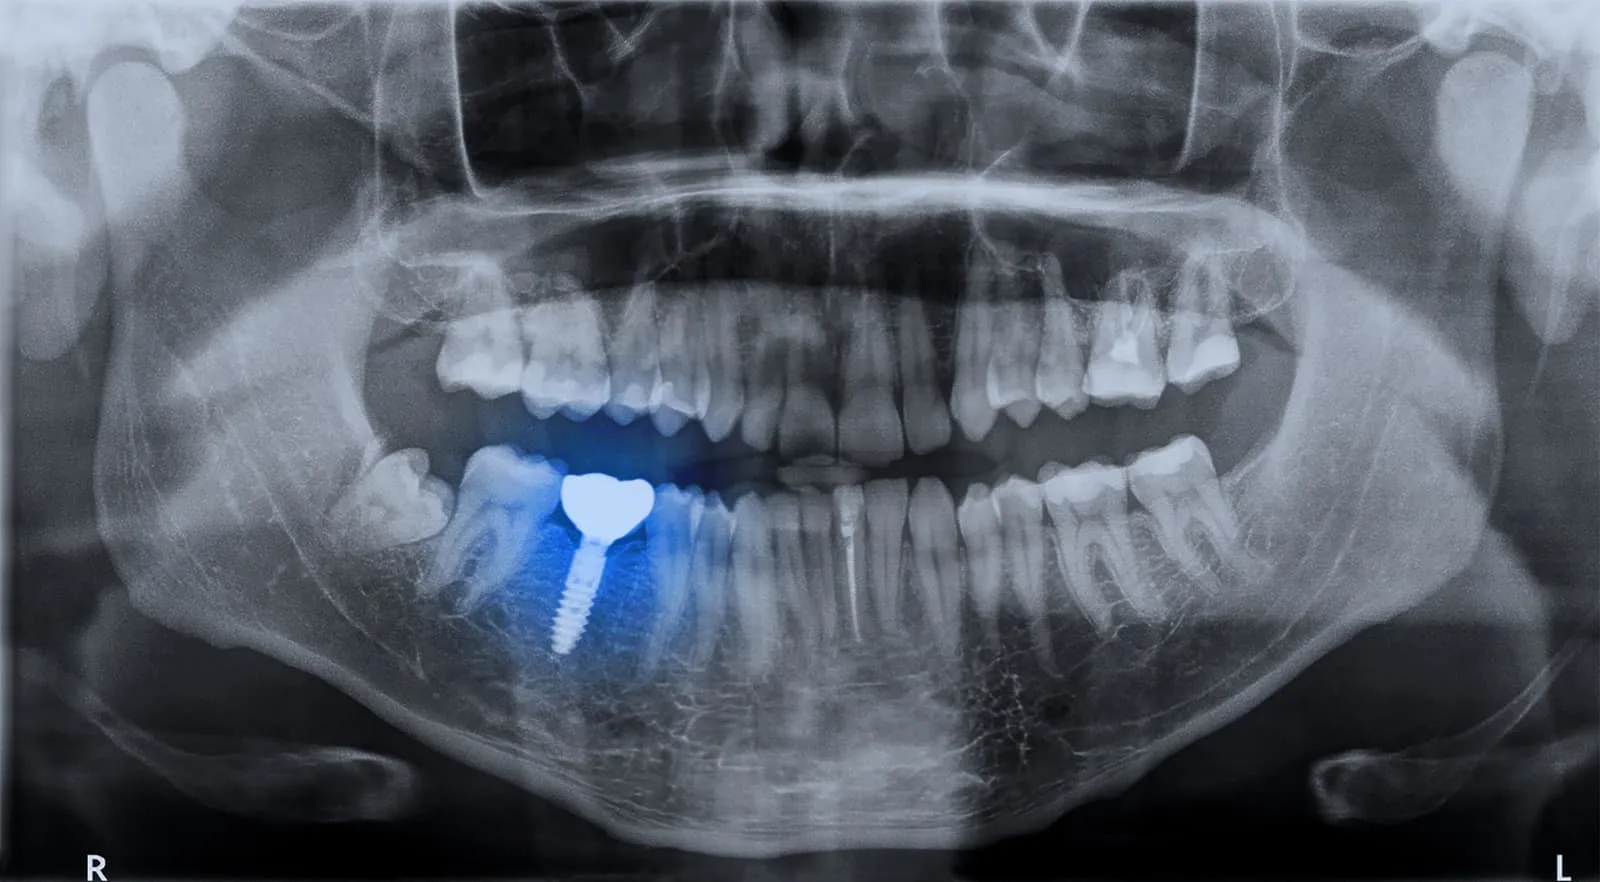

Are Dental Implants Safe for MRI? Best Dental Implants in Bengaluru Orthodontic Braces Mri Safety — getting an mri with braces is generally safe when appropriate precautions are taken. — however, patients with many types of orthodontics, including metal braces, retainers and some palatal expanders, may undergo mr imaging, as these are sufficiently secured to the teeth and have been shown to be safe on clinical mr scanners at 1.5t and 3t (tesla).. Orthodontic Braces Mri Safety.

Is It Safe For Someone With Dental Implants To Go For MRI Scans? Orthodontic Braces Mri Safety is it safe for my child with braces to have an mri? Yes, depending on the body part that needs imaging. — getting an mri with braces is generally safe when appropriate precautions are taken. — however, patients with many types of orthodontics, including metal braces, retainers and some palatal expanders, may undergo mr imaging, as these. Orthodontic Braces Mri Safety.